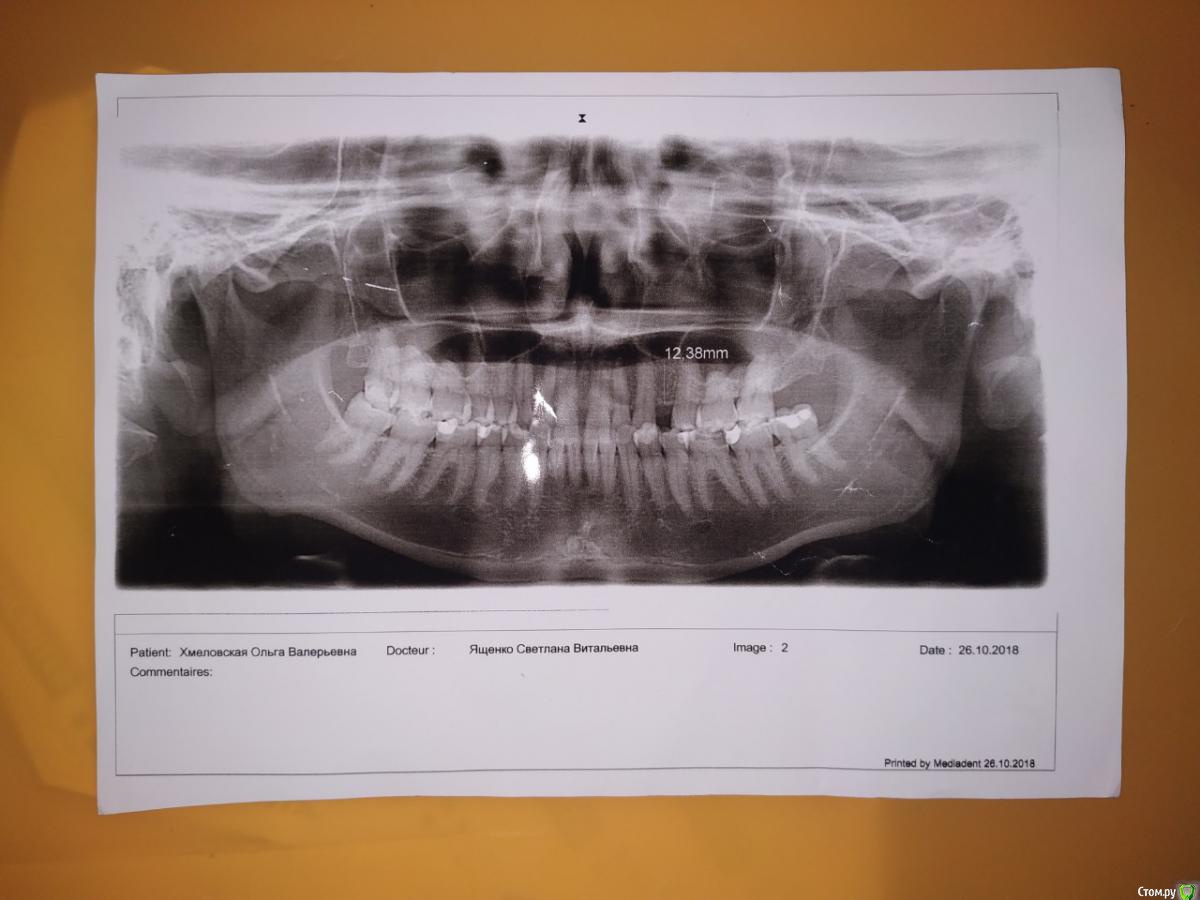

В ноябре стало побаливать ухо. И болеть нос и  как бы небо с левой стороны. Над тремя зубами. Где то внутри. Подтекание между зубами стало каждый день очень кислое. Пошла в челюстно-лицевое отделение. Сделали томограмму. Снимок зубов. здорова. Ни кист, ничего нет. Боль странная то ноющая. то отдает в ухо. То проходит. С утра просыпаюсь как правило не болит. Открываю широко рот болит где то внутри. Ощущение что там где 6 верху что то нарывает,пульсирует и дергает. Небольшая припухлость десны где 6 и 7. Определили что звук издает зуб при нажатии -6 . Послали к лору и невропатологу и парадантологу. Невропатолог-здорова.

Парадантолог сказал с карманами все впорядке. Выписала Метровиол и попить линкомицин месяц. Витамины, кальций. Сделали чистку зубов. Визуально здорова. Проверили живы ли зубы.Все  зубы отреагировали. Зубы живые. Проверяли по ощущению как бы током. Парадантолог отправила к хирургу чтобы я заказала ночную капу и снизила ночную нагрузку на зубы. В 2010 году  долго лечили 4 тоже слева. с 2008 года. Потом вырвали сказали нужно остеомиелит. И до сегодняшнего времени ничего не болело. Болит какой то корень(как бы пульсирует) и болит уже нос. На снимке пазухи чистые.

Тянет как бы небо там где корни в положении лежа. Неприятно. 5,6,7 все корни заходят в пазуху.

Врача-стоматолога ищите, лоры здесь второстепенны, вероятность совпадения очень маленькая. Попросите врача осмотреть верхнюю и нижнюю шестёрку, диагноз ставится после нехитрых проб. Проблему вы преувеличиваете. Снимки малоинформативны.